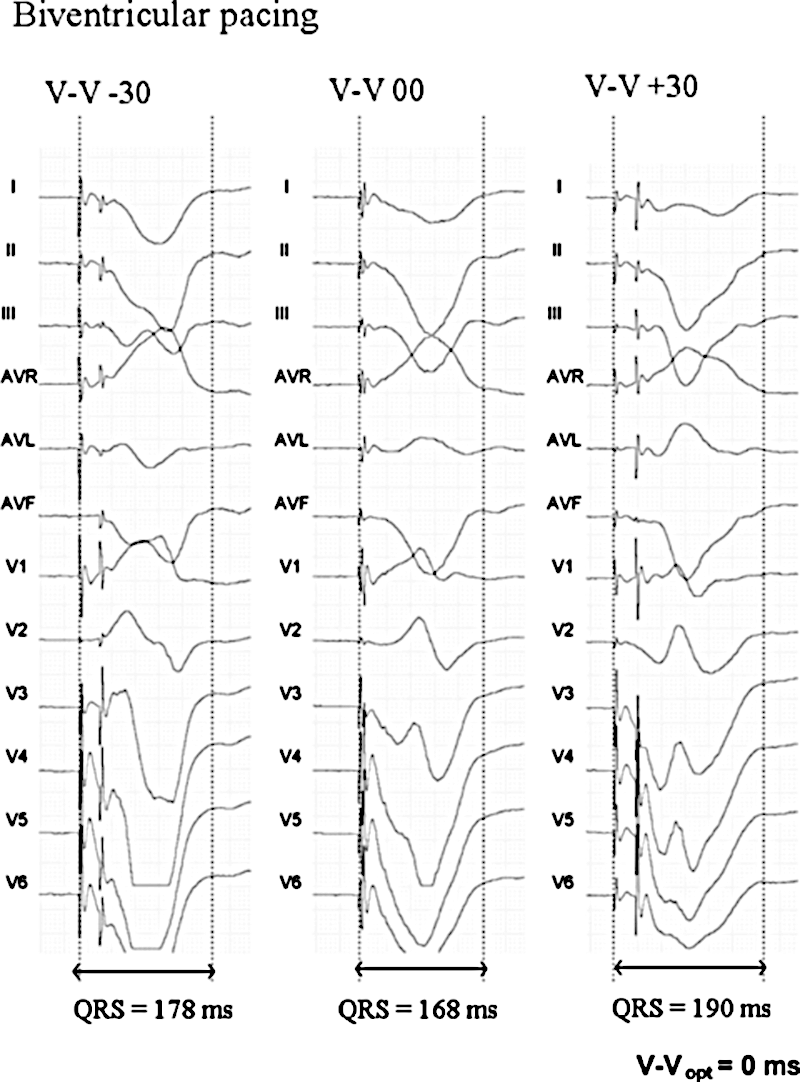

More narrowing of QRS associated with better response

Vidal B, Tamborero D, Mont L.. Brugada J. Electrocardiographic optimization of interventricular delay in cardiac resynchronization therapy:a simple method to optimize the device. J Cardiovasc Electrophysiol. 2007;18:1252–1257